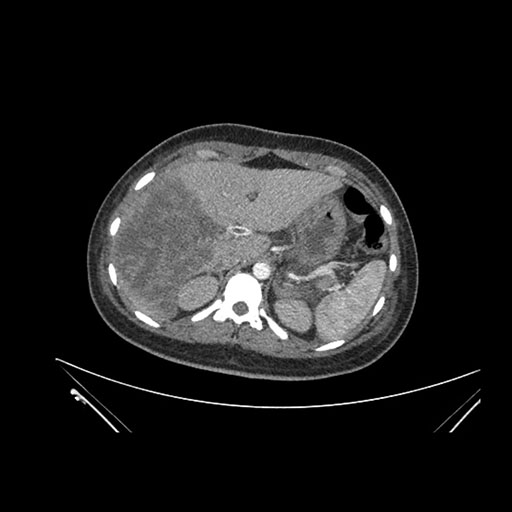

Imaging Analysis

Look through the patient's CT scan to identify any areas of concern for the necessary procedure.

Axial Arterial

Based on initial findings, which issue(s) would you be most concerned about?